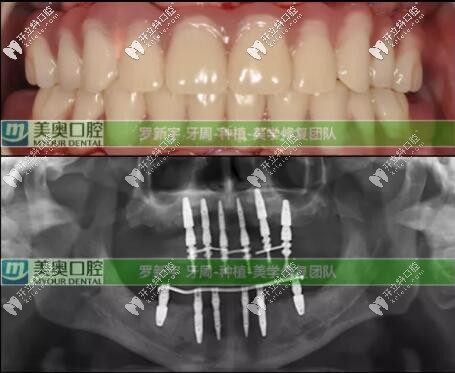

接著就是種植牙修復(fù)計(jì)劃:根據(jù)臨床上的口腔數(shù)據(jù),根據(jù)顧客的實(shí)際情況選擇了Straumann? Pro Arch無(wú)牙頜種植修復(fù)解決方案,拔除全部松動(dòng)的余留牙,雖然犧牲可能有點(diǎn)大,但換來(lái)的是全口好牙還有自信。

全口即刻負(fù)重種植就是:在當(dāng)天種植并完成臨時(shí)修復(fù),PS:臨時(shí)修復(fù)是指臨時(shí)牙冠。為患者帶上臨時(shí)牙,可實(shí)現(xiàn)當(dāng)天吃蘋(píng)果的愿望。即刻修復(fù)就是這么快。后期又進(jìn)行了為期六個(gè)月的復(fù)診和跟蹤治療;

六個(gè)月后口腔檢查評(píng)價(jià):種植體全部存留、臨時(shí)修復(fù)體存留、終末修復(fù)體(長(zhǎng)久性的牙冠)存留;可以說(shuō)這次種植修復(fù)是很成功的。